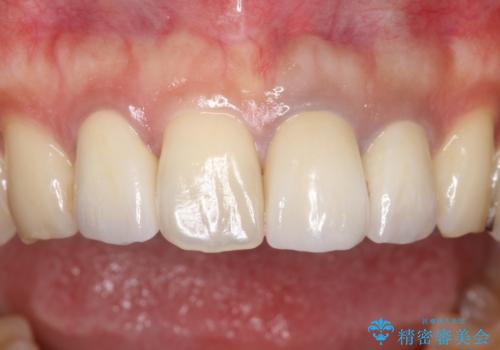

セラミックと矯正を組み合わせることにより、審美的にも機能的にも改善することができました。

- 全体的なガタガタと前歯をきれいにしたいとのことで来院されました。

インビザラインにて歯並びを整え、上顎の前歯にセラミックを装着する計画としました。